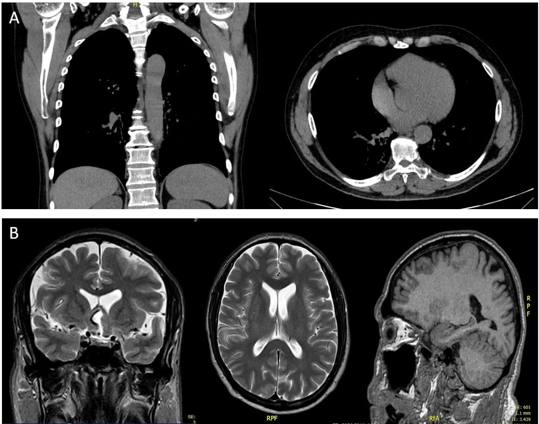

Chest X-ray imaging revealed micronodules (Fig. 3a), and an MRI of the skull showed hypodense areas predominantly in the anterior brain and preseptal cellulitis (Fig. 3b).

Liver transaminases were within normal parameters. With these results, disseminated ocular, periorbital, pulmonary, and lymph node paracoccidioidomycosis was considered. An evaluation by infectious disease specialists and neurosurgeons was requested based on these findings. The treatment plan provided by the infectious disease specialist includes fluconazole tablets of 200 mg every 6 hours, trimethoprim-sulfamethoxazole 160/800 mg every 24 hours, and amphotericin B deoxycholate 50 mg IV every 24 hours, all administered intravenously over a three-week period in the hospital.